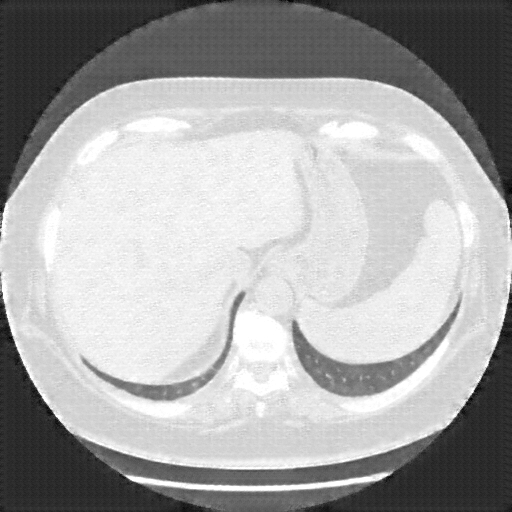

Generated VENOUS CT scan (A→B translation)

Mediastinum window (WL 40, WW 400 β†’ Low βˆ’160, High +240)